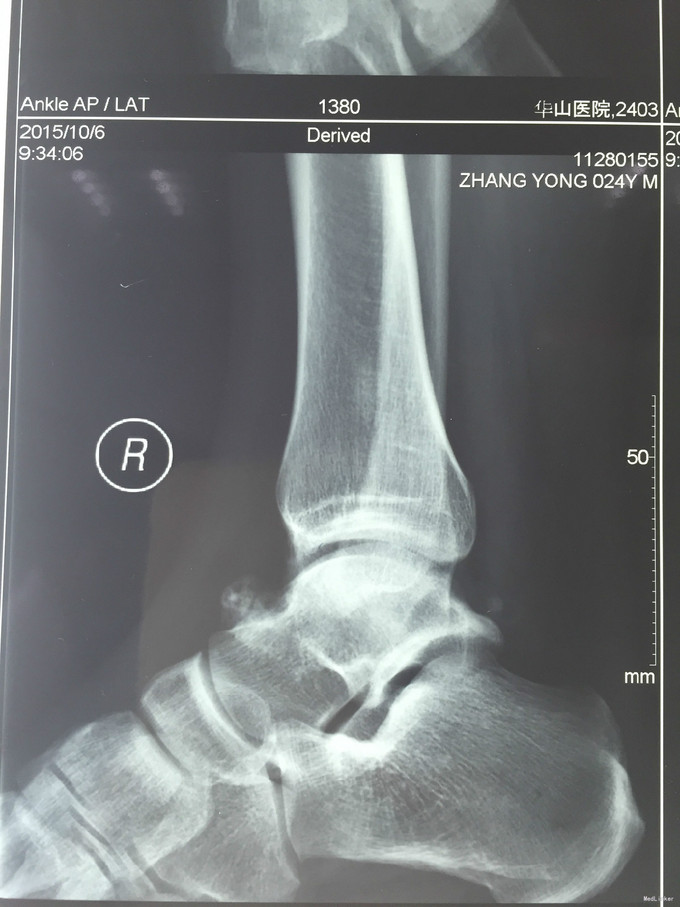

主诉:右踝扭伤后疼痛3年,伴活动受限2年。 现病史:患者男性,24岁。3年前,患者运动时扭伤右踝,无出血。患者当时至外院就诊,予消炎药物保守治疗,疼痛缓解。2年余前患者出现右踝活动受限,以背屈受限明显,伴右踝疼痛,无发热、盗汗,无其它关节痛,无晨僵等。2年来患者自觉右踝疼痛及活动受限症状逐渐加重。外院查MRI示:右胫骨远端前方骨质增生、右距骨前方骨性隆起、右踝关节内积液。我院查右踝X线示:右距骨前下方骨质密度增高、右胫骨前缘骨质增生。于我院就诊,门诊拟"右踝前方撞击综合征、右距骨骨软骨瘤、右踝滑膜炎"收入院。

查体:左下肢、双上肢肌力及活动度正常。右腓肠肌稍萎缩,右踝无明显肿胀。右踝关节跖屈、背屈受限,右踝内侧及前方关节间隙压痛(+)。ADT(-),下蹲提踵试验(+),内翻试验(-)。右腓肠肌肌力、肌张力、感觉正常。 辅查:见现病史。图片见下。

入院诊断:右踝前方撞击综合征、右距骨骨软骨瘤、右踝滑膜炎 治疗:入院完善术前检查后行右踝关节镜下滑膜清理+前方撞击成形+距骨骨软骨瘤切除。